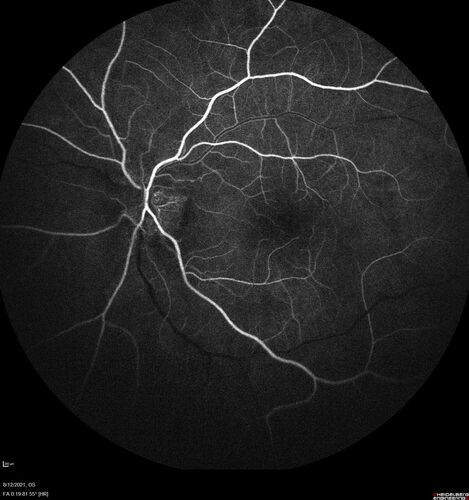

Neuroretinitis left eye - recovered with no therapy - possible B pertussis

57 year old female The patient has had blurred vision in the left eye and there is a haze across the top of the vision.  This started about 2 weeks ago.  The right eye is OK.  She has sleep apnea and uses the machine.  The left eye is becoming more and more painful for the last two weeks.  The pain is like a stabbing in the eye that comes and goes.  She also has some pain on eye movement.  The patient has been going to Moffit for possible reconstructive surgery for the lymphedema.

PMHx – Sleep apnea, Breast Cancer, Adult lymphedema,

Meds: Gabapentin

VA OD: Dcc20/25-1

VA OS: Dcc20/100-2

AC quiet OU.  1 + NS cataract OU

IOP: TP: OD:15 OS:17